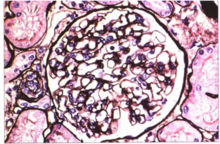

1.光鏡系膜細胞的瀰漫性增生為系膜增生性腎小球腎炎的基系膜增生性腎小球腎炎理特點,可伴有系膜區的增寬。此病變通常影響80%以上的腎小球,多數腎小球病變程度相似,稱為瀰漫性增生。早期以系膜細胞數增多為主,在中等病變中每個系膜區的系膜細胞數為4~5個。而在較嚴重的病變中,每個系膜區的系膜細胞數多在5個以上,系膜區還可見單核細胞浸潤。Masson染色約50%的病例可見系膜區嗜復紅免疫複合物沉積。腎小球毛細血管壁正常,毛細管腔開放較好。大多數病例腎小管、間質組織及腎內小動脈正常。